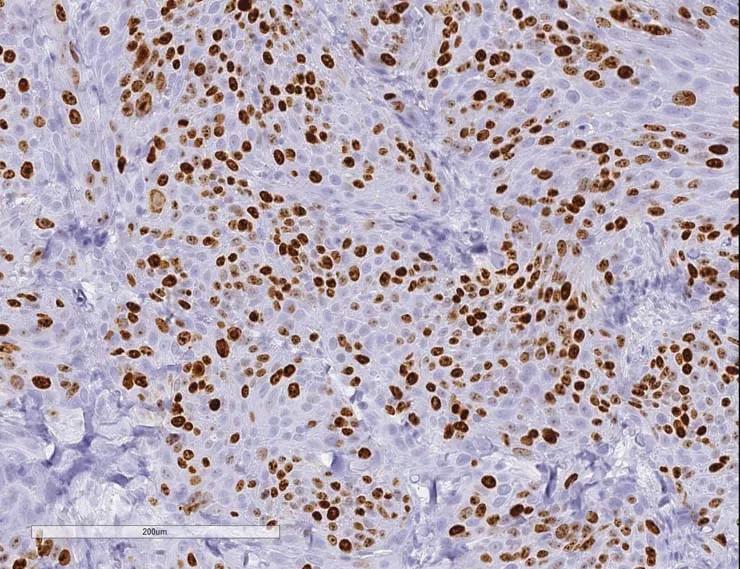

Low-passage samples retain the heterogeneity and fidelity of human cancers. Engrafted tumors derived from a patient with a bladder urothelial papillary carcinoma demonstrate high concordance of tumor morphology, compared to low passage PDX tumor TM00015.

Figure C) Tumor cells of patient origin within the xenograft-stained positive using an anti-human antibody for Ki67.